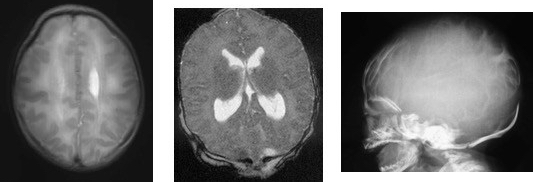

encéphalocèle occipitale associée à des malformations multiples du tronc cérébral et de l’encéphale ; noter l’hypoplasie mandibulaire : syndrome de Pierre Robin d’origine centrale, absence de ventilation spontanée à la naissance. - malformations rachidiennes de type Klippel-Feil et hémivertèbres